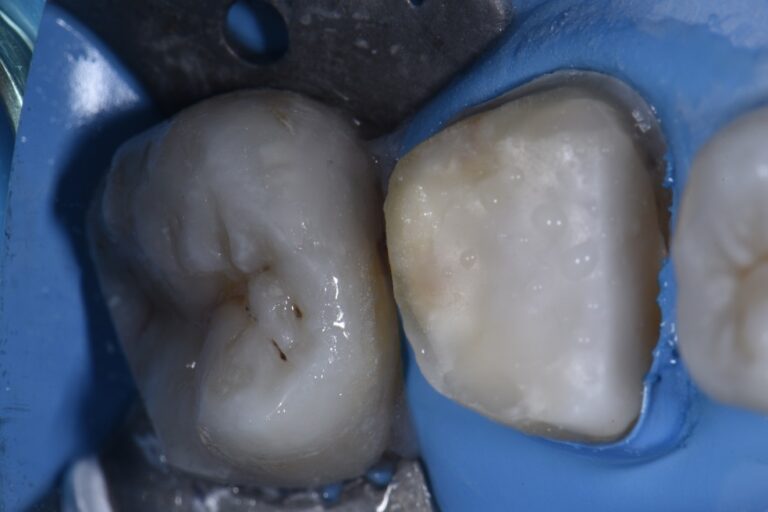

Three Essential Tips for Bonding to Zirconia Dentistry Today